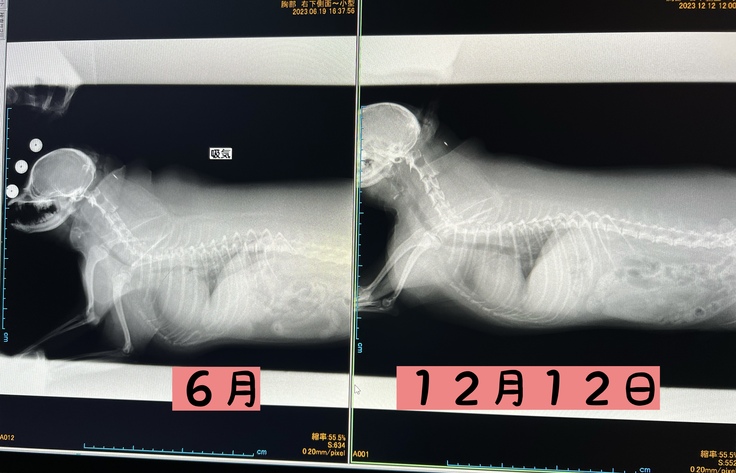

12月12日かかりつけ医にてレントゲンを撮ってもらい、

気管が正常に広がっていることを確認してもらいました!